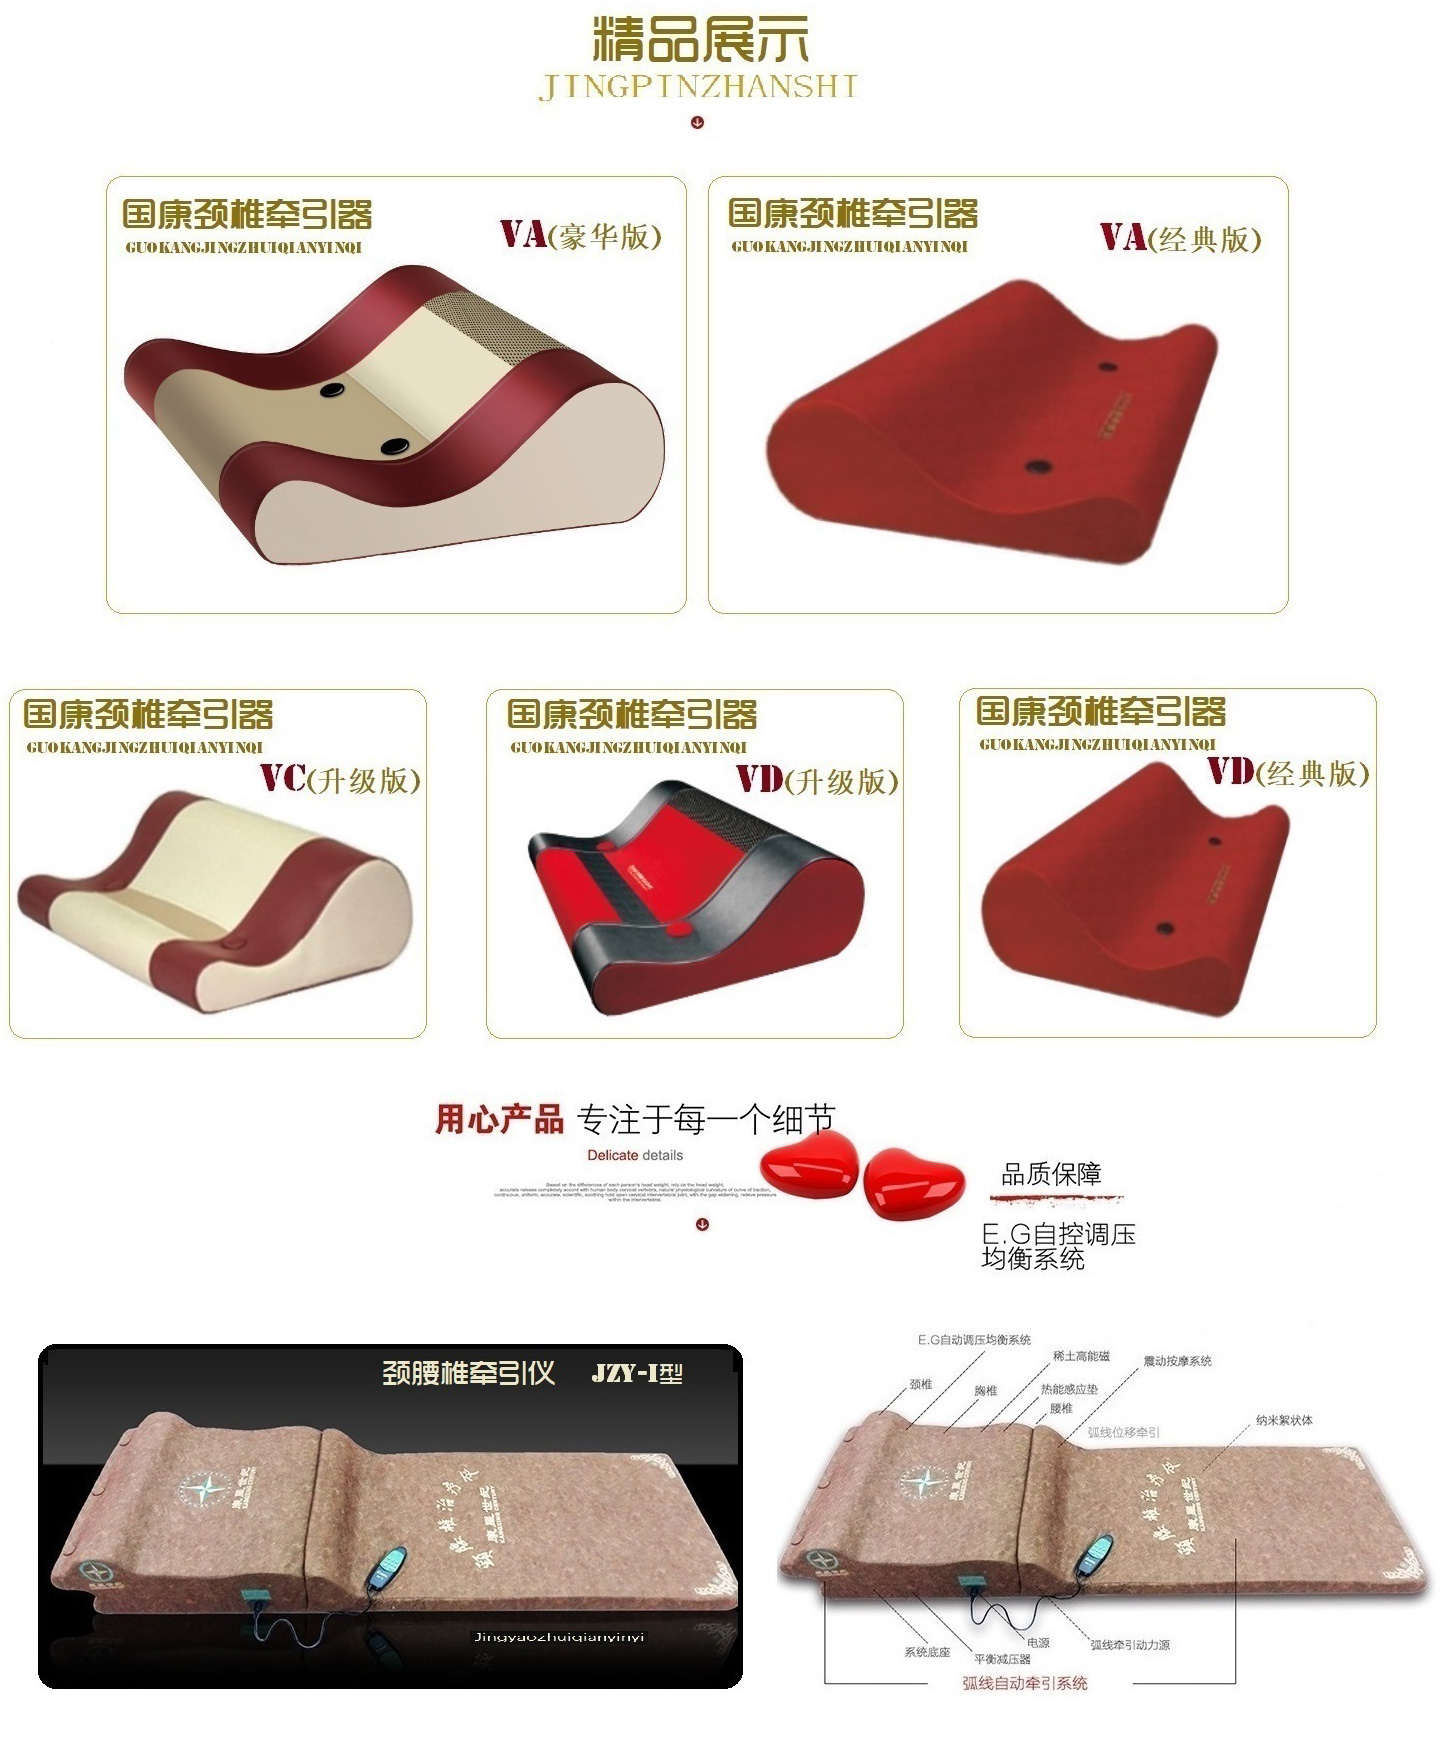

1.1 产品名称:(通用名称)颈椎牵引器 (商品名称)国康颈椎牵引器(以下简称牵引器)

1.2 规格型号:JZY—VA、JZY—VB、JZY—VC、JZY—VD、JZY—VE

1.3 生产许可证:京药监械生产许20030090号

1.4 产品注册号:京药监械(准)字2013第1260298号

1.5 执行标准号:YZB/京0035-2013 Q/CPKXS0001-2013 《JZY系列颈椎牵引器》

JZY系列颈椎牵引器是根据力学原理,将人体颈椎和头部的重力与磨擦力实时转换为自然牵引力,产生位移, 从而加大颈椎椎间隙,减轻对神经根的压迫,解除肌肉痉挛,缓解疼痛;对神经根型、 椎动脉型、交感神经型颈椎病引起的颈肌僵硬、头痛、头晕、手指麻木等临床症状具有缓解作用。

该产品对神经根型、椎动脉型、交感神经型颈椎病起到牵伸治疗作用;作为临床治疗的辅助治疗产品。

位移量:22mm±20%; 形变量:16mm±10%。

各型号使用功能提示.:VA型:高的一侧为牵引时用,低的一侧为睡眠时使用;VC.VD型高处为牵引使用;产品特点:国康颈椎牵引器利用人体头部和颈椎的重力转换为弧线位移牵引力;

产品效果:当人体颈椎与牵引体弧面贴合时,当人体颈椎与牵引体弧面贴合时, 一推/一拉立即产生弧线位移力,位移牵引力高22mm;使颈椎椎节被均衡牵开, 力度更适中更安全方便,充分利用自然休息和睡眠时间,恢复颈椎生物力平衡。